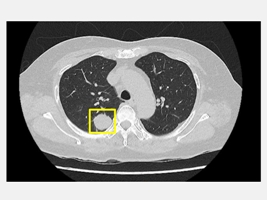

50歲的吳先生平時生活作息規律,從不抽菸,也沒有肺癌家族史,原以為自己身體健康的他在一次健康檢查中,經由低劑量電腦斷層(LDCT)意外發現右側肺部有一顆約2公分大小的腫瘤。吳先生前往仁愛長庚合作聯盟醫院(大里仁愛醫院)尋求醫療專業協助,經由胸腔暨心臟血管外科林宜右醫師詳細評估後,建議進行肺臟腫瘤切除手術,並且採用目前先進的「單孔達文西機器人微創手術」技術,在三天內順利出院。

林宜右醫師說,現代醫療的進步,是希望讓每一位病人都能以最小的負擔,獲得最完善的治療。並提醒,肺癌初期多無明顯症狀,凡是有吸菸史或家族病史的人,應定期接受低劑量電腦斷層篩檢(LDCT),及早發現及早治療,才能守護健康。